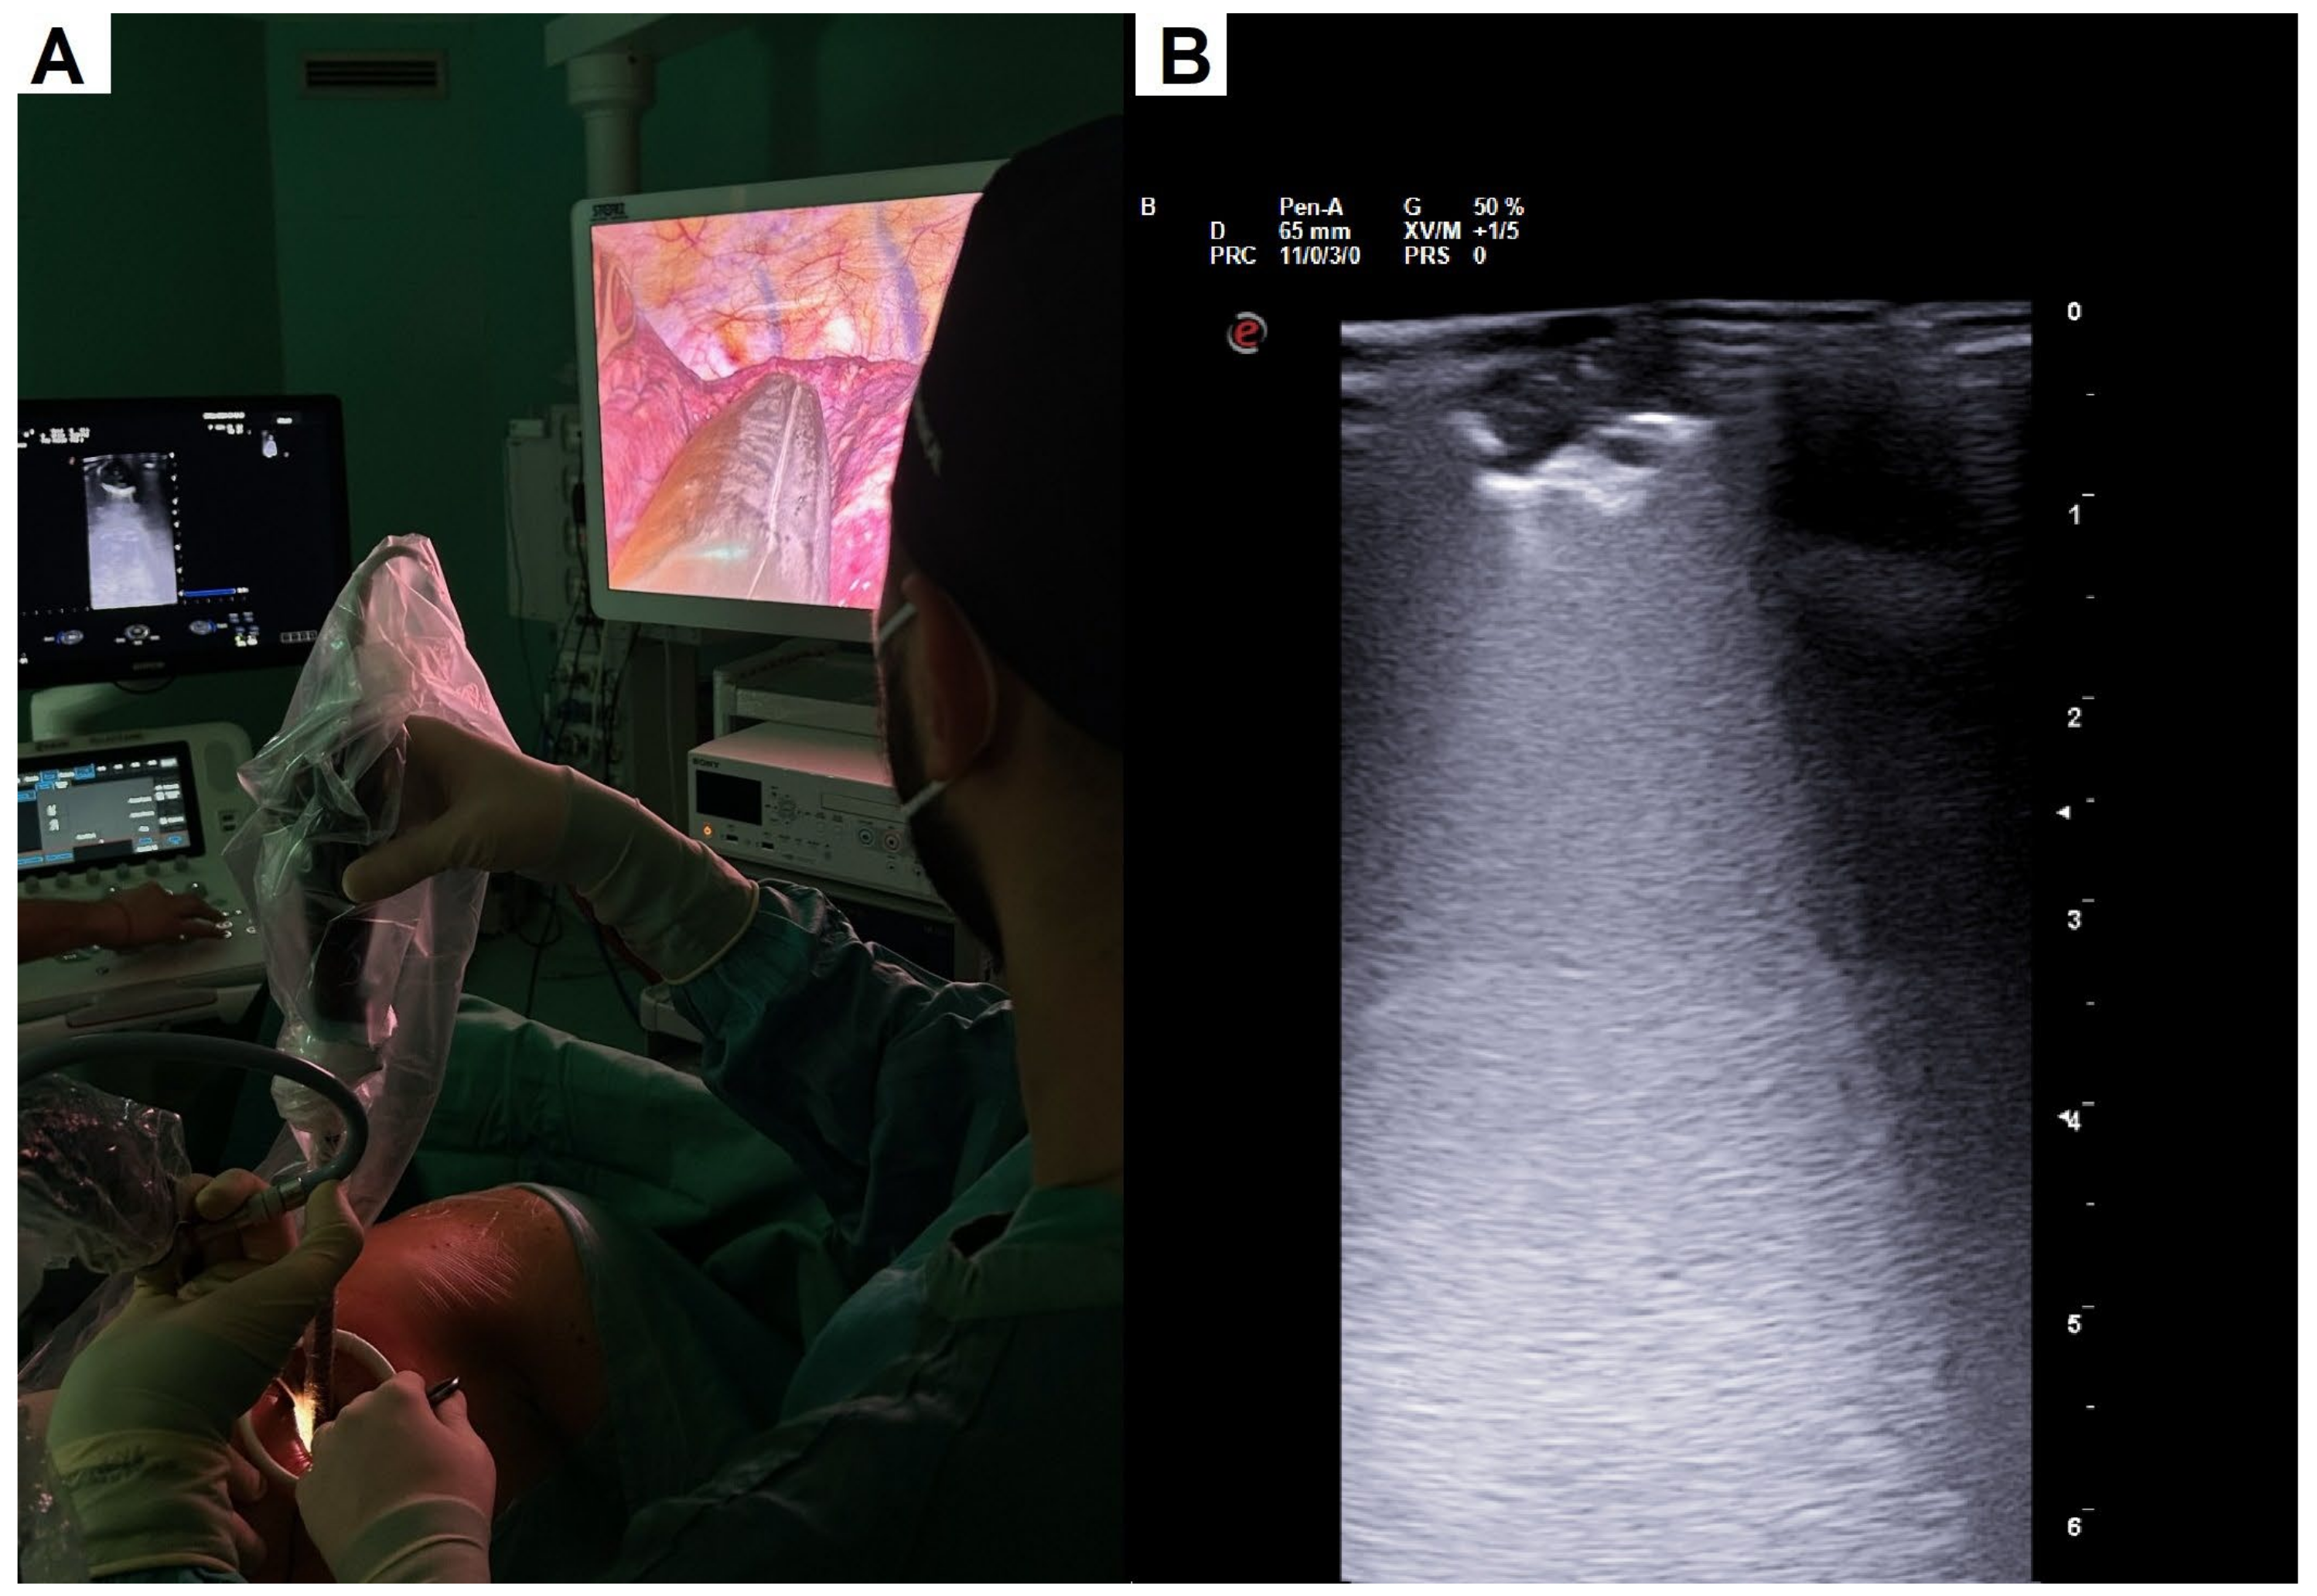

2.2. Surgical Details